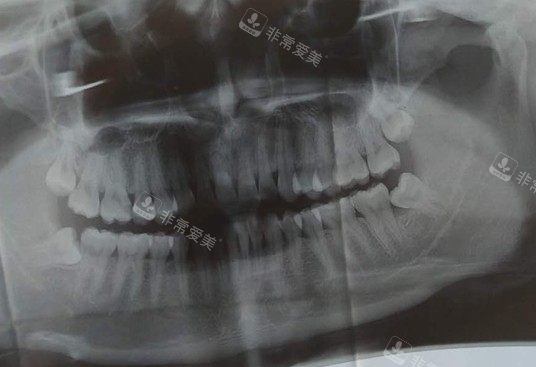

口腔牙齿ct照片